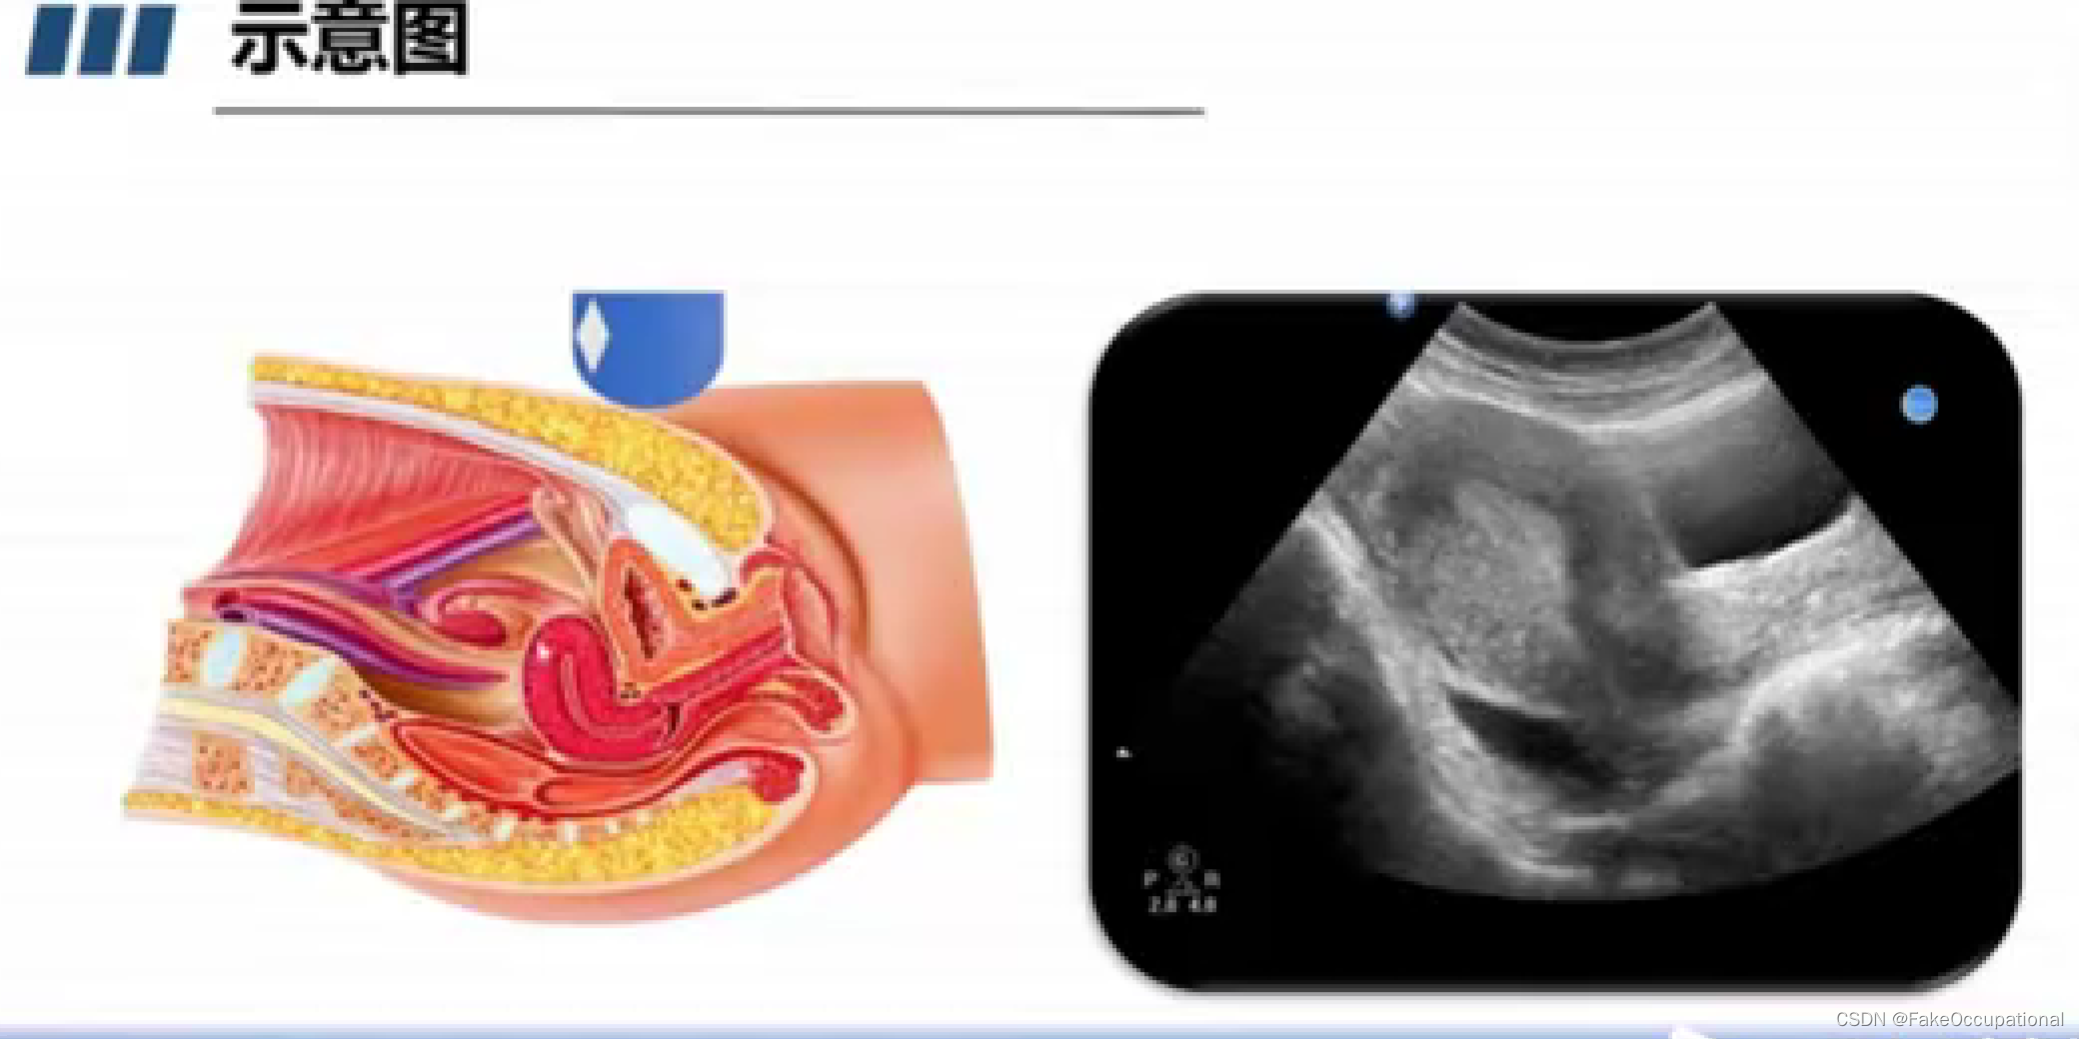

妇科超声(已和谐)

正常子宫和卵巢声像图